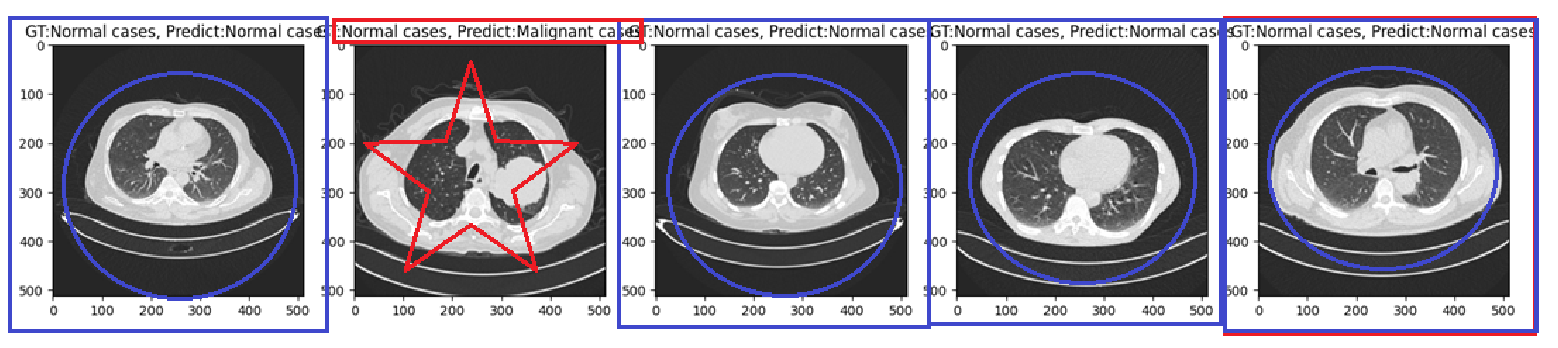

plt.figure(figsize=(20,5))

for idx in range(5):

img = Image.open(test_file_list[idx]).convert('RGB')

img_src = test_data_transform(img)

x_tensor = img_src.unsqueeze(0)

result = model.predict(x_tensor)[0]

gt = test_file_list[0].split('/')[-2]

pt = model.names[torch.argmax(result.probs.data).item()]

plt.subplot(1, 5, (idx+1))

plt.title(f'GT:{gt}, Predict:{pt}')

plt.imshow(img)

plt.show()

5개중에 1개빼고는 모두 잘 맞춘것을 확인할 수 있습니다.

여기서 중간에 PT가 아니라 Predict로 나온이유는 위에 title에서 predict로 썼기때문입니다.

pt로 변경해준다면 pt가 됩니다.